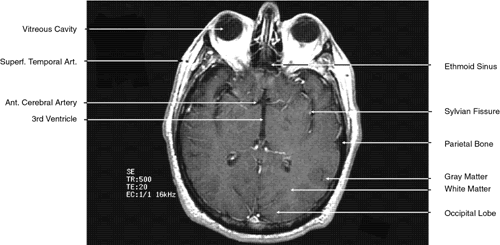

The globe is shown in Figure 12. The orbit and periorbital structures are shown in Figures 13 through 16, and the optic canal is shown in Figures 17 through 26. The cavernous sinus and optic chiasm are shown in Figures 27 and 28, and the posterior visual pathway and cranial nerves are shown in Figures 29 through 33.

Fig. 32. A. Axial computed tomography soft tissue image at the level of suprasellar cistern. B. Axial computed tomography soft tissue image at the level of thalamus. C. Axial T1-weighted image at the level of thalamus.